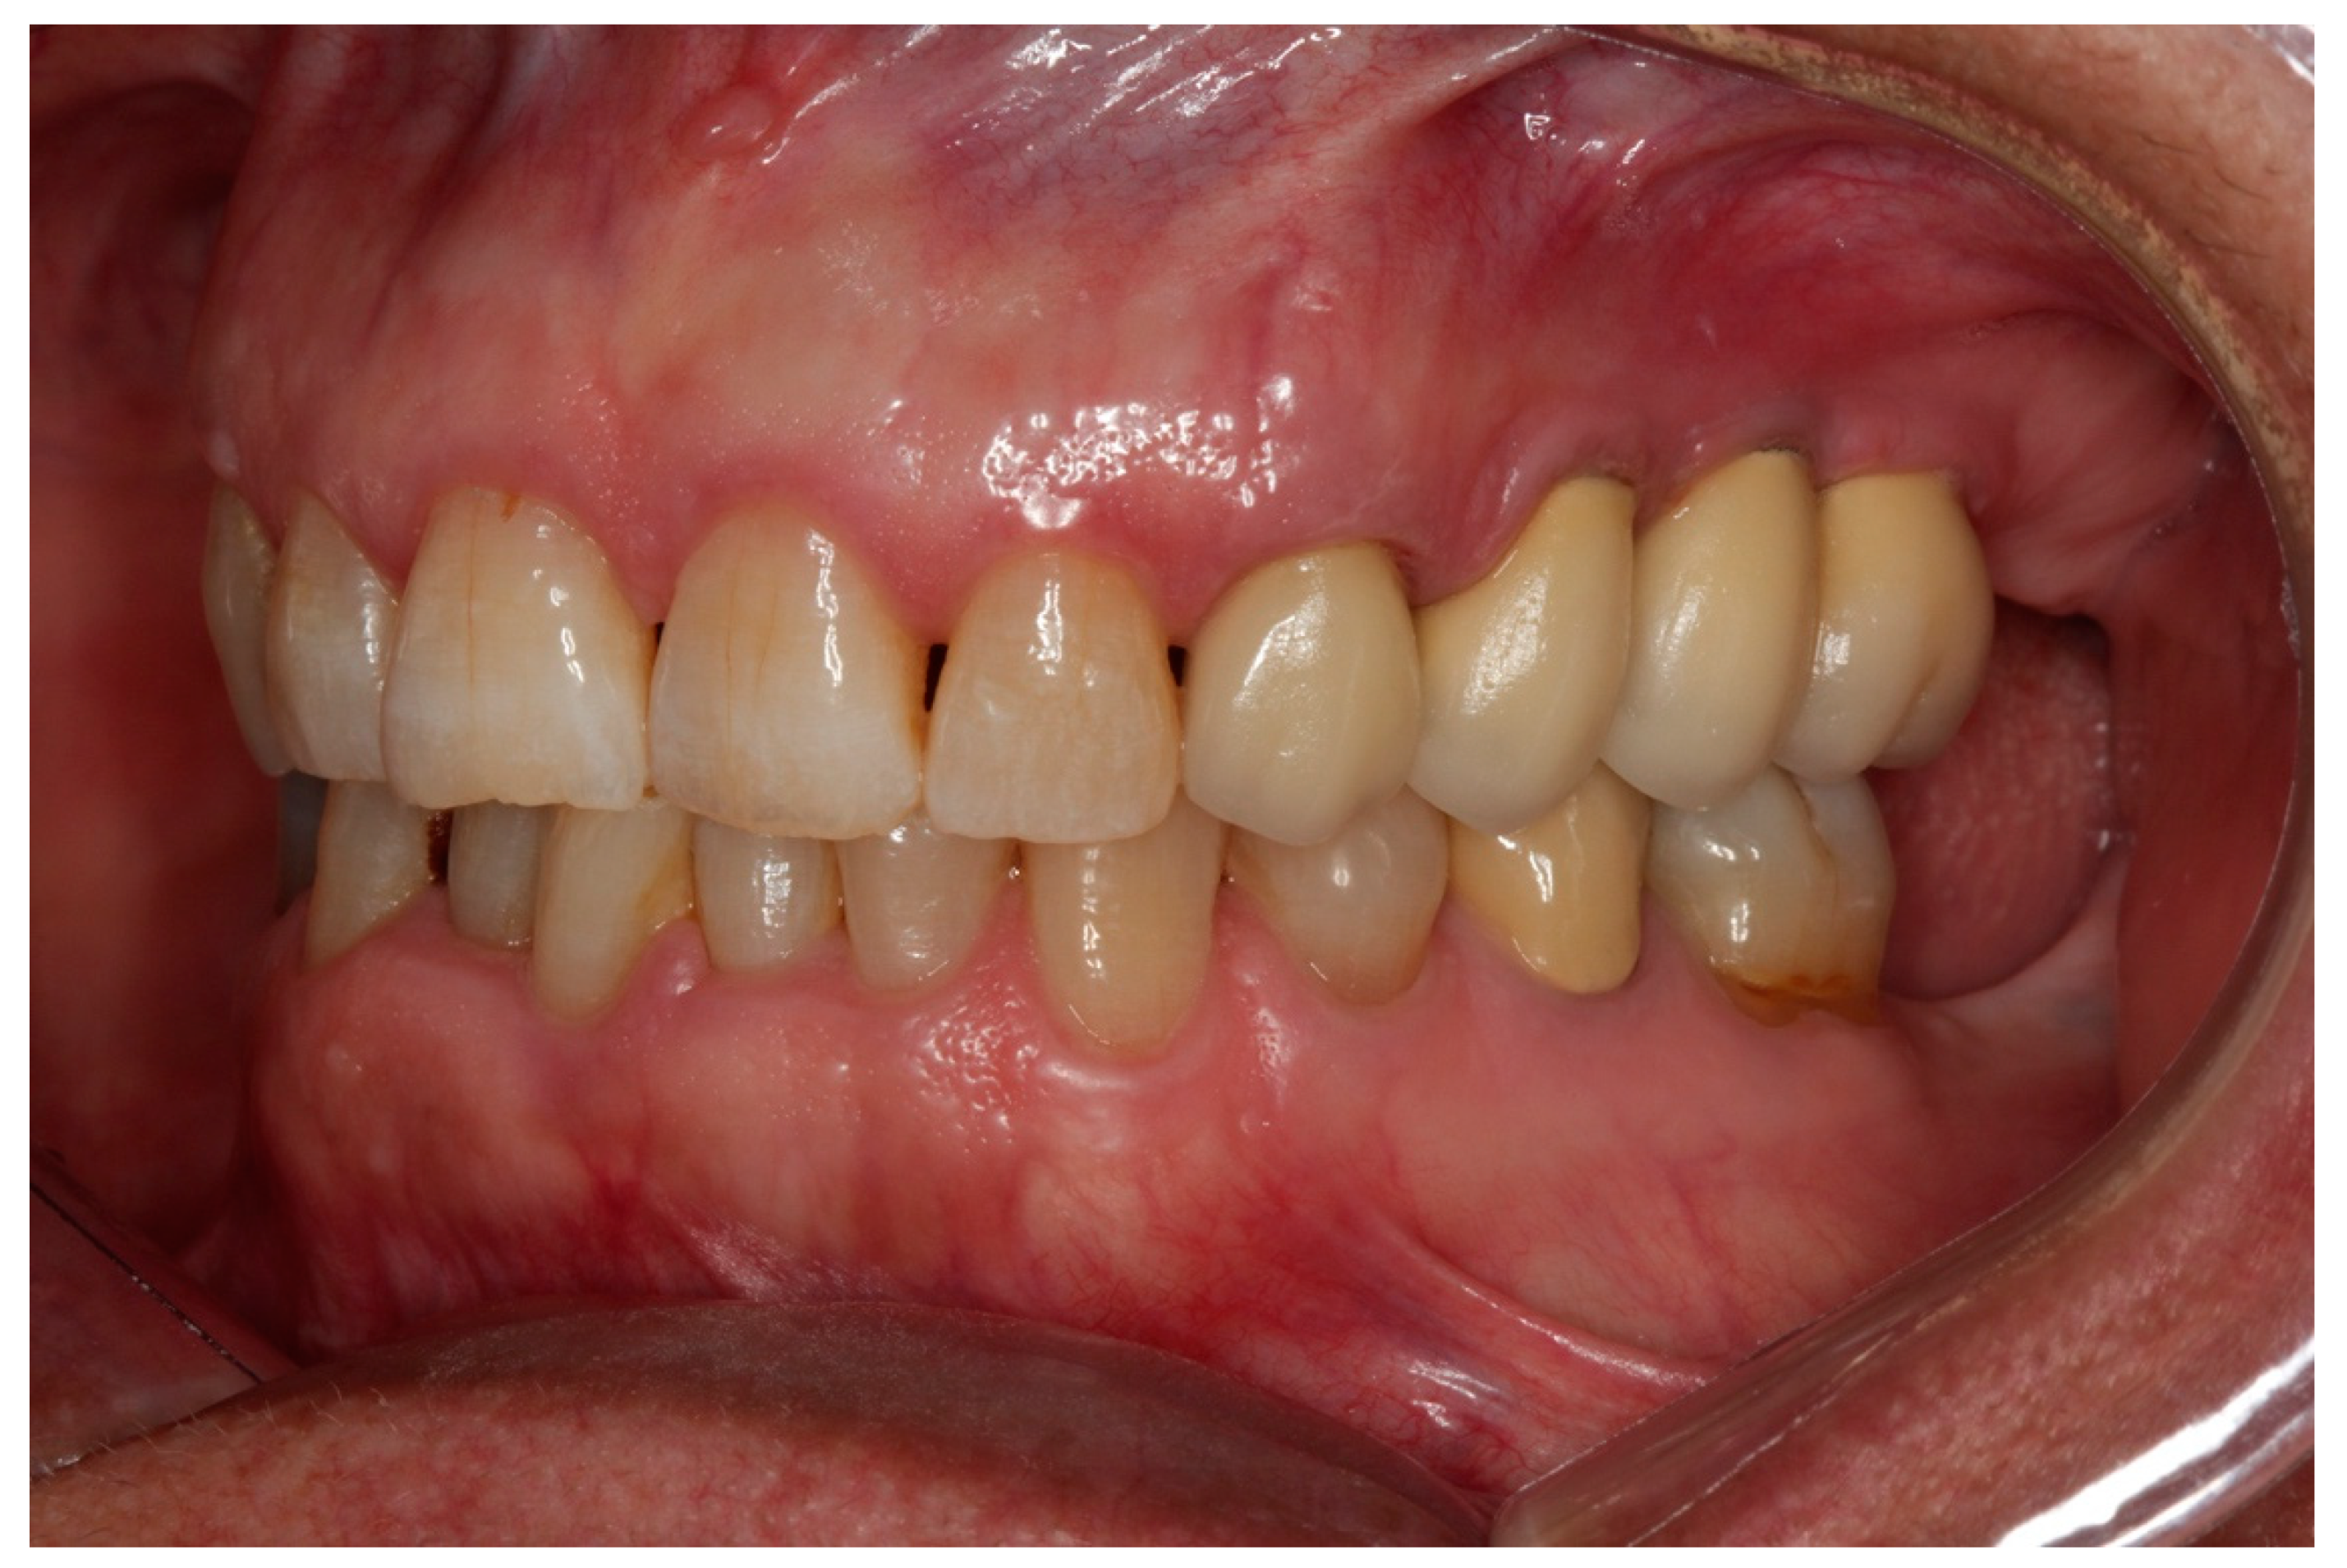

2.1. Patients

2.2. Surgical Procedure